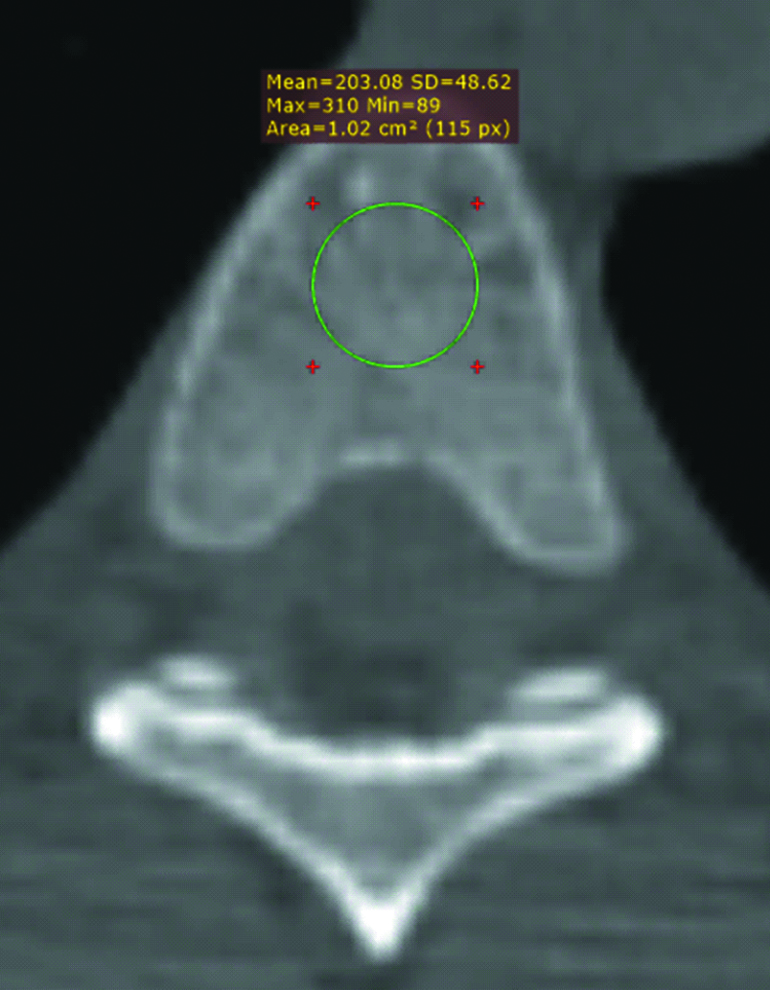

Высоту, ширину, передне-задний размер и рентгеновскую плотность тела TVI позвонка определяли на компьютерном томографе Optima 660 (рисунки 1–3).

Рисунок 3. Пример измерения рентгеновской плотности тела позвонка у мужчины 23 лет.

Figure 3. Example of X-ray density measurement of the vertebral body in a 23-year-old man.